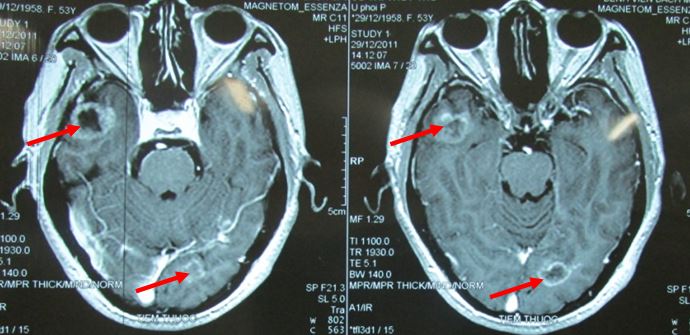

- Chụp MRI sọ não

Hình 2: hình ảnh MRI sọ não cho thấy di căn não đa ổ

Hình 8: U di căn não đa ổ trước điều trị

Hình 9: tổn thương não tiêu biến hoàn toàn, lâm sàng hoàn toàn bình thường